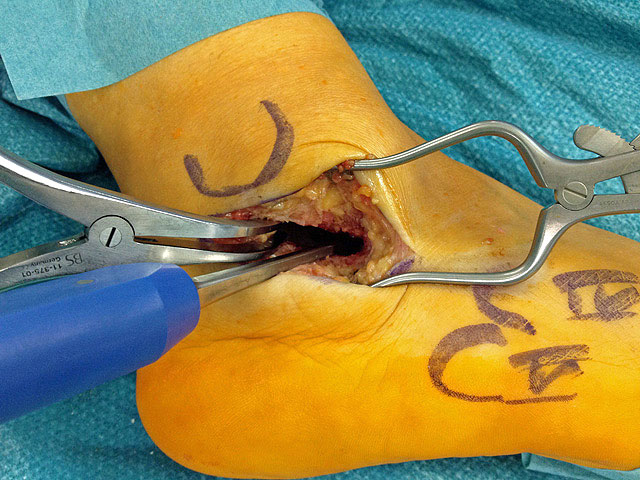

Je nach Operationsziel wird die Arthrodese des Subtalargelenks in verschiedenen Modifikationen durchgeführt. Ist der Rückfuß orthograd ausgerichtet, so erfolgt sie als in situ Fusion, d.h. ohne Korrektur Änderung der Rückfussachse. Liegt eine Rückfuß-Fehlstellung vor, kann diese durch ein additives oder substraktives knöcherndes Vorgehen korrigiert werden 12. Die Fixation der Arthrodese erfolgt üblicherweise mit (kanülierten) Schrauben die über den Tuber calcanei eingebracht werden 3. Eine zweite Schraube zur Sicherung der Rotationsstabilität wird optional über den Processus anterior calcanei im Talushals verankert 4. Der am häufigste verwendete Zugang zum unteren Sprunggelenk verläuft lateral subfibular, alternative Zugänge sind medial oder posterior möglich 56. Ist keine relevante Korrektur notwendig kann der Eingriff auch arthroskopisch durchgeführt werden 78.

Abbildung 1

Abbildung 2